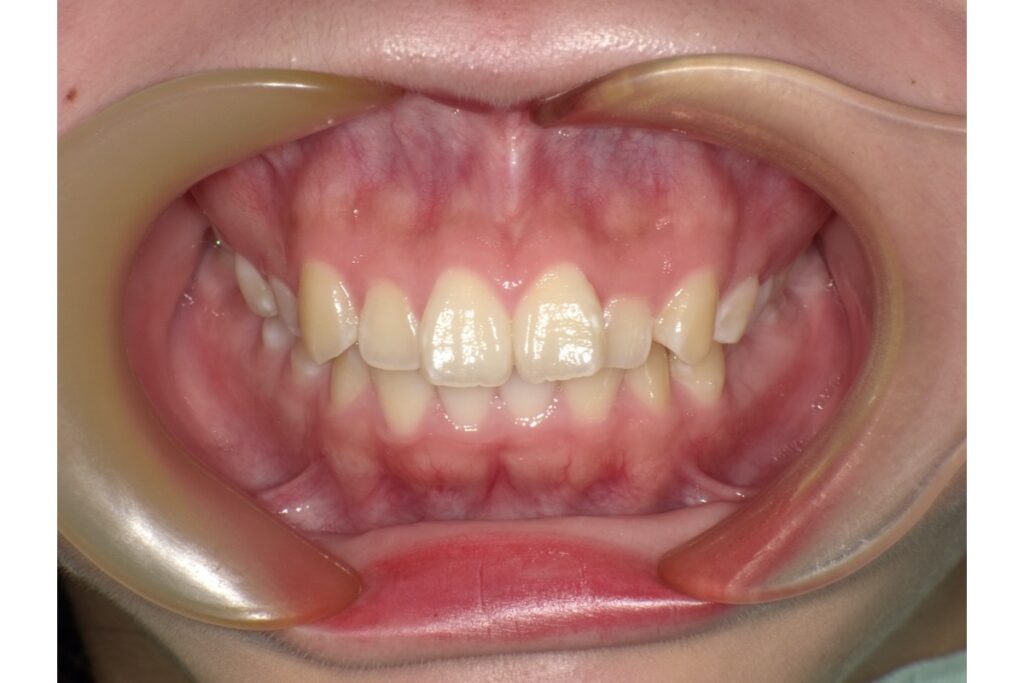

治療終了時の歯並び写真がこちらです↑

治療期間は、約1年半。その期間中に2回マウスピース作り直しをしています!

治療前後の写真を見比べると、前歯の引っ込み具合がよく分かります。

歯を抜いて治療を行っているので、横から見たときの変化がとても分かりやすいかと思います。歯だけではなく、横顔も口元がスッキリしますよ。